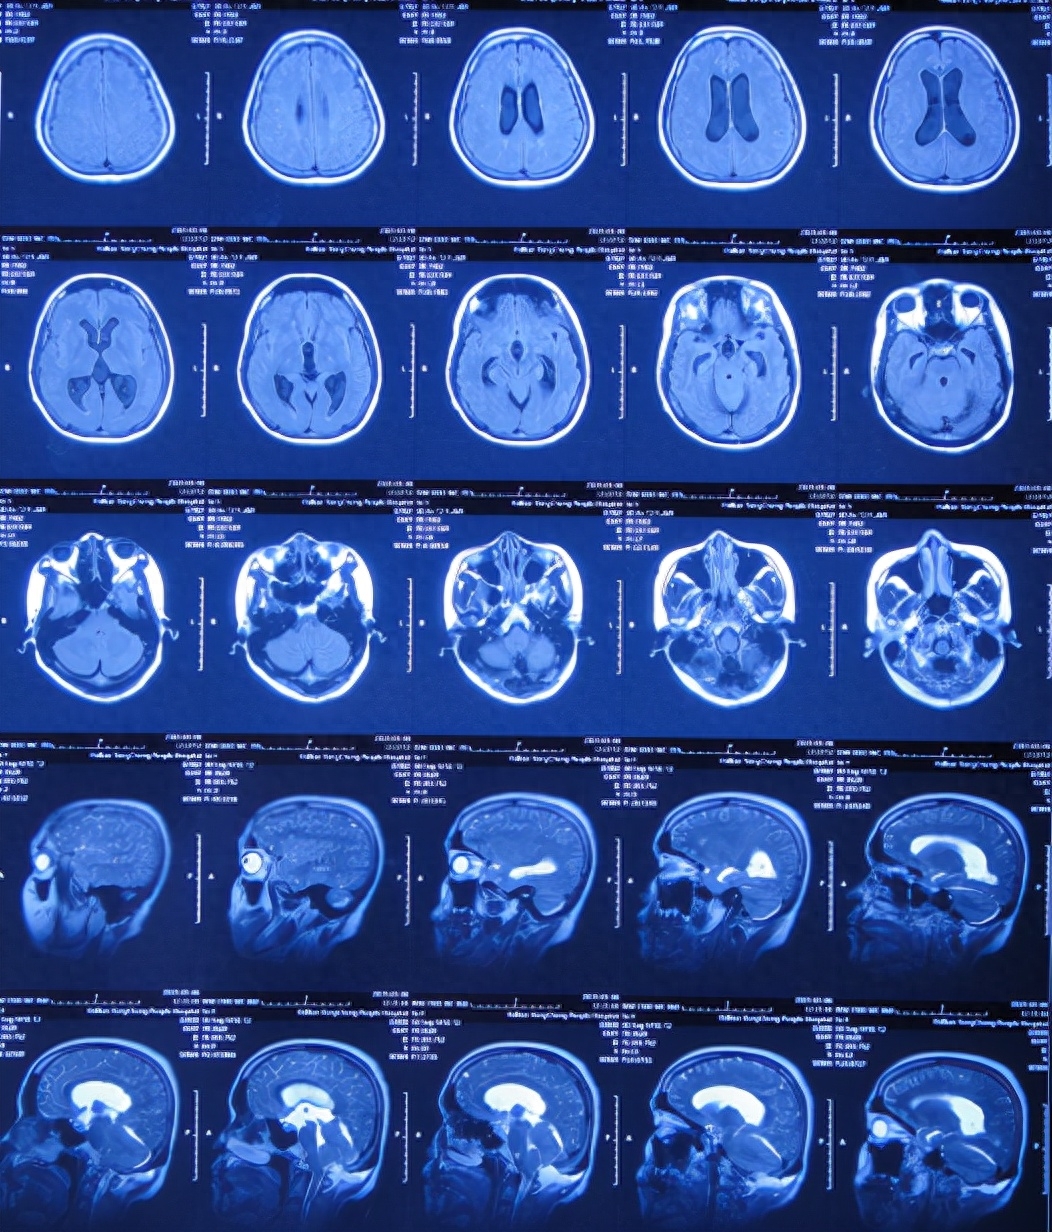

患者2019年2月初,因数次出现发作性黑蒙,2019年2月10日就诊于当地的河南省永城市某医院,查头颅CT未见明显异常(图-1);次日再查头颅核磁、颈椎核磁(图-2、图-3)后发现小脑扁桃体下疝畸形合并脊髓空洞。

图-2:2019年2月12日头颅核磁

图-3:2019年2月13日头颅核磁

小脑扁桃体下疝减压术后20天即2019年3月6日,查头颅、颈椎核磁发现仍有脊髓空洞(图-8、图-9)。

图-8:2019年3月6日头颅核磁

图-9:2019年3月6日头颅核磁

入院治疗42天即2019年5月9日,头痛和体温均已完全正常近1月,查颈椎核磁示脊髓空洞有变小(图-16)。

图-16:2019年5月9日颈部核磁

出院后8个月即2020年1月9日,来院复查。复查时:身体完全正常(图-19),查颈椎核磁:无异常(图-20)。

图-20:2020年1月9日颈部核磁